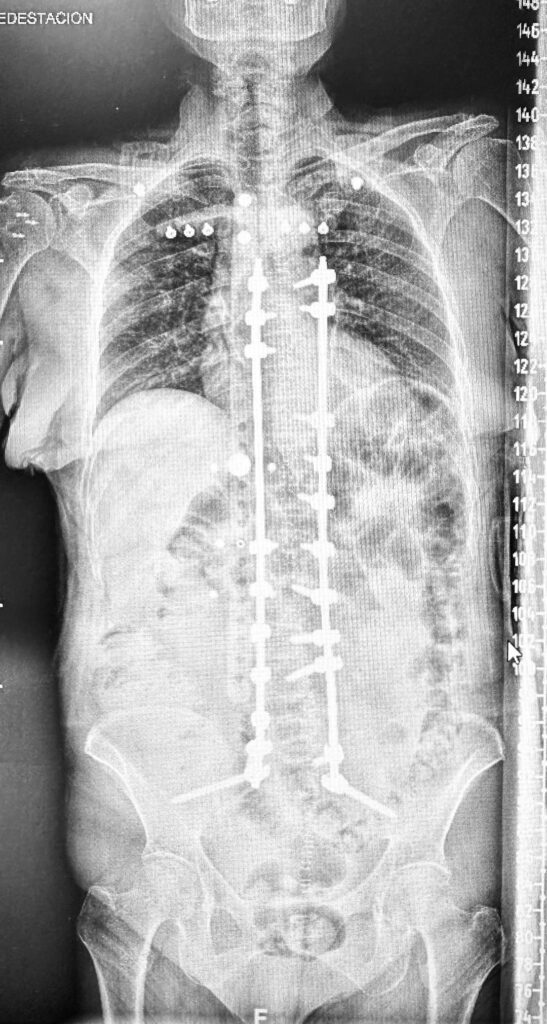

El procedimiento comienza con un estudio exhaustivo de imágenes como radiografías, tomografía computarizada (TC) y resonancia magnética (RM). Con esta información, se diseña una guía tridimensional que facilita la colocación de tornillos pediculares y otros dispositivos de fijación. Durante la cirugía, el Dr. Botella-Asunción emplea estas guías junto con sistemas de navegación intraoperatoria para garantizar una corrección precisa de la escoliosis y la descompresión de las estructuras nerviosas afectadas.

La experiencia del Dr. Botella-Asunción, combinada con el uso de estas tecnologías de última generación, asegura resultados óptimos, devolviendo calidad de vida a sus pacientes y marcando un estándar en el tratamiento quirúrgico de deformidades espinales.